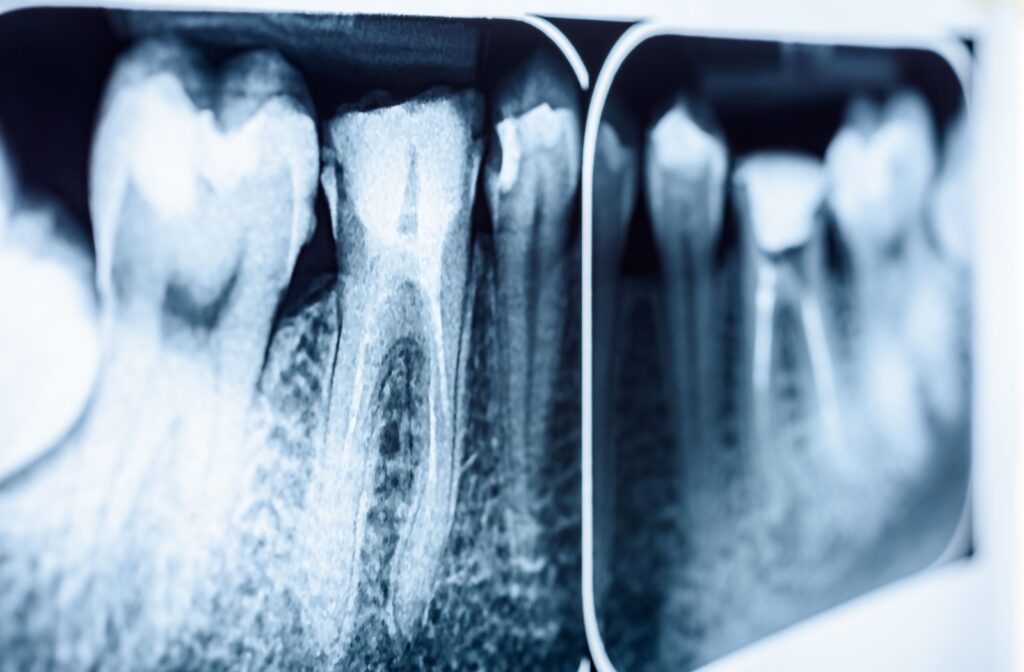

What to Know if a Root Canal Is Suggested

The Goal Is to Save Your Natural Tooth

A root canal isn’t about causing pain; it’s about relieving it. Root canals remove the infection from a tooth, which not only stops the toothache but can also save your tooth from needing extraction. Keeping your own natural teeth is almost always the preferred choice for long-term oral health.